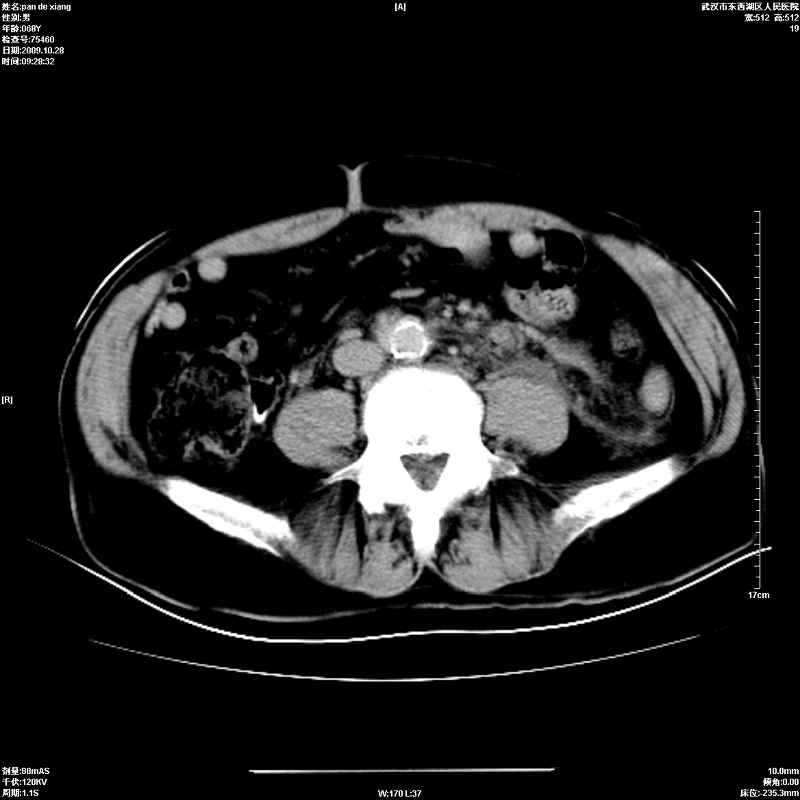

以下是引用杀毒软件在2009-10-28 20:41:00的发言:[br]结合临床考虑---白血病双肾改变或淋巴瘤。

以下是引用zxl51642在2009-10-29 9:59:00的发言:[br]结合临床“单克隆免疫球蛋白血症”,考虑双肾为继发损害并肾功能不全(尿中大量igg及少量iga、igm等大分子免疫球蛋白滤出所致继发损害),椎前软组织肿块为髓外造血。与浆细胞瘤有区别,平扫时有战友说的很清楚。